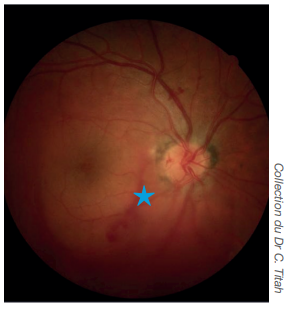

Œdème papillaire

Engainement blanchâtre des vaisseaux